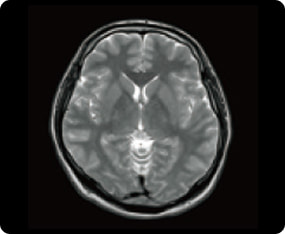

頭部MRI検査の症例画像

脳(大脳)